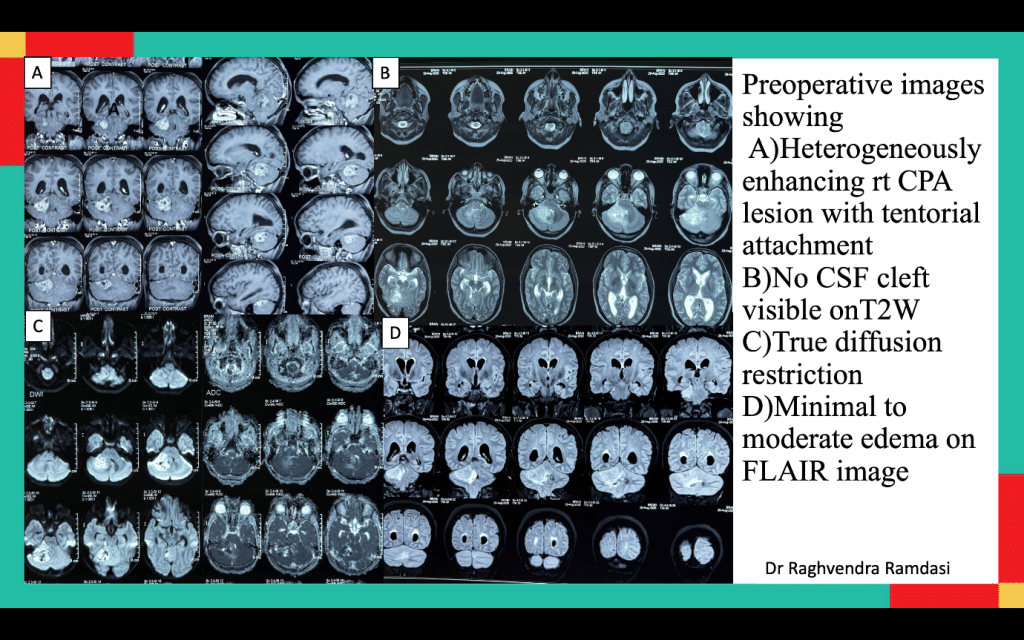

MRI findings of her brain revealed a right CPA mass appearing extra-axial with tentorial attachment. The lesion was isointense on T1, heterogeneously hyperintense on T2, and showed strong, patchy post-contrast enhancement. Diffusion-weighted imaging (DWI) demonstrated marked restriction, indicating high cellularity. Also, moderate cerebellar edema, mild hydrocephalus and importantly- no T2 hyperintense CSF cleft were detected between tumor and cerebellum. Audiometry revealed mild sensorineural hearing loss.